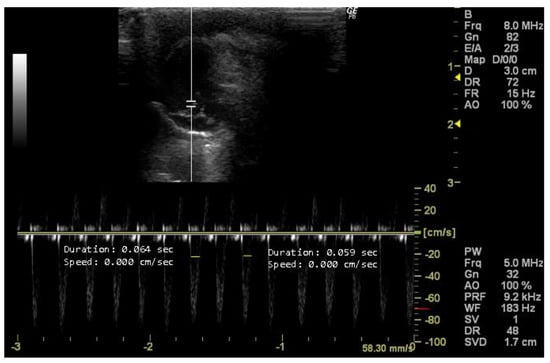

3.4.3. Doppler Mode

- How to measure HR

- How to measure PAAT